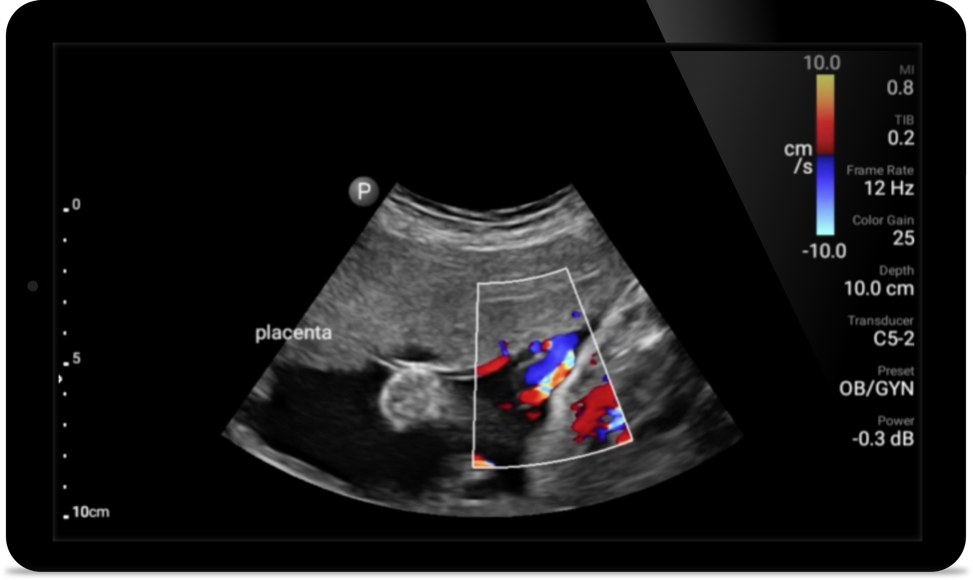

Reduzca las complicaciones en procedimientos guiados por aguja

El ultrasonido portátil Lumify para anestesiología le ayuda a visualizar claramente la definición de los bordes con la colocación de la aguja, los nervios circundantes, los vasos sanguíneos y los planos fasciales.

Lleve el ultrasonido a la cabecera del paciente

El uso de Lumify junto a la cama de sus pacientes puede ser una herramienta valiosa para determinar el estado del contenido estomacal y puede reducir el riesgo de aspiración pulmonar. En conjunto, esto puede reducir el riesgo de complicaciones por anestesia.